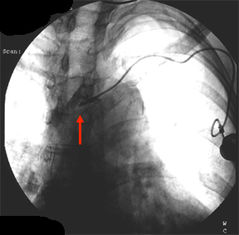

Im Röntgen sieht man den dislozierten Katheter und die Kontrastmittelextravasation ins Mediastinum. Dorthin wurde auch das hochgradig gewebetoxische Adriamycin infundiert.

- Pinch off Syndrom bei 2%. Dabei wird der Katheter zwischen 1. Rippe und Clavicula abgeschert. Es kommt zuerst zur Extravasation bei Injektionen, dann zur Katheterfragmentation mit Embolisation in rechten Vorhof, rechten Ventrikel oder die Lunge. Solange das Katheterfragment noch im Herzen liegt, kann es oft transfemoral mit einer Schlinge extrahiert werden. Aus der Pulmonalarterie kann es nur durch eine offene Operation mit HLM entfernt werden.